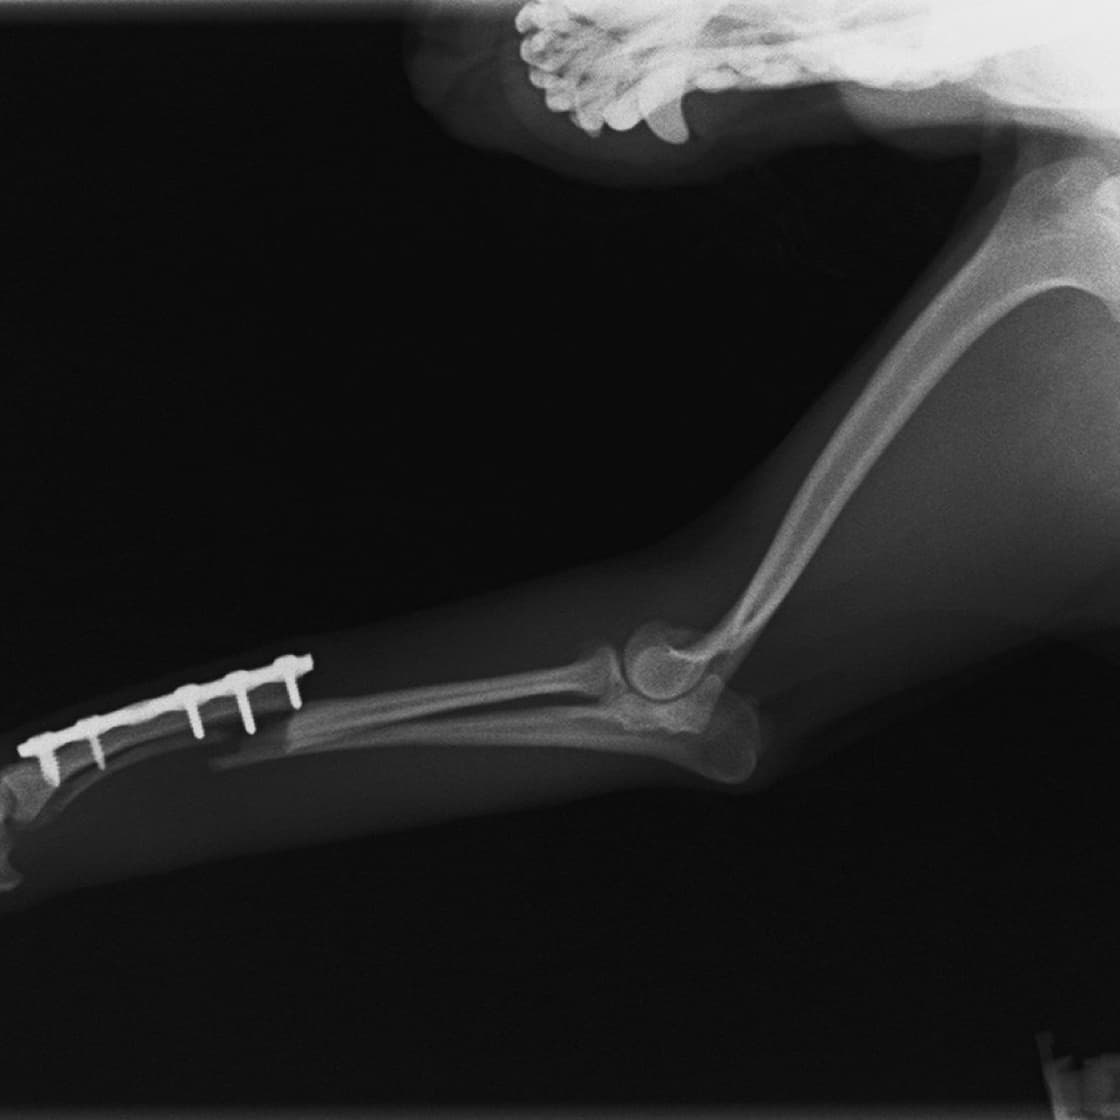

症例3:キルシュナーワイヤーのピンニングによる整復

ペルシャ猫 11ヶ月齢 雄

他院にて左大腿骨遠位の成長板骨折(salter-harrisⅠ型)が認められており、治療相談を目的として来院。当院にて、キルシュナーワイヤーを用いたピンニングにより骨折部位の整復を行いました。術後の経過は良好で、現在も経過観察中です。

術前レントゲン

術後レントゲン

機器

Arthrex社のターゲティングデバイスを用いてピンニングの位置を調整することで、確実な固定を行っています。当院ではこの手術器具以外にも、人の手術にも使用される様々な器具を導入し、手術精度を高め、また医療メーカーと新しい器具の開発、試作にも取り組んでおります。